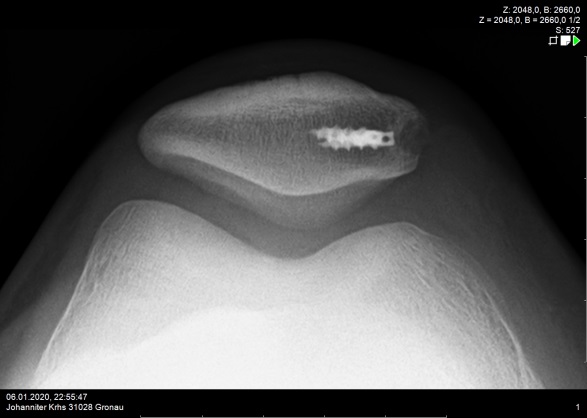

Darstellung einer MPFL Plastik bei zentrierter Kniescheibe

In surgical interventions, the so-called MPFL (medial patellofemoral ligament) is the focus of treatment, because it is the main stabiliser of the patella (kneecap) in flexion degrees close to extension and works against a large part of the outward forces. This ligament is torn in about 90% of cases after a patellar dislocation. During the operation, it is replaced by a tendon from the patient's own body (gracilis or quadriceps tendon), which is tensioned in the course of the MPFL. If there are other factors that promote instability, these are also included in the therapy. For example, it may be necessary to create a new sliding groove in the femur for the kneecap in order to achieve bony stability.